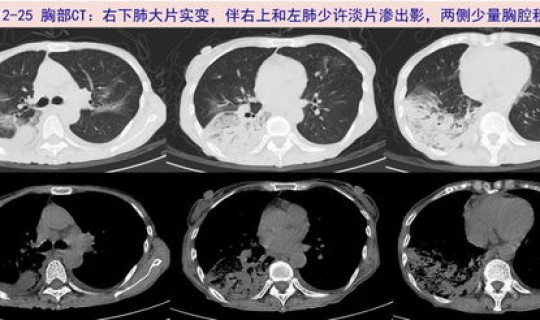

随着症状的加重 ,病人会出现呼吸困难 、胸闷、气短,甚至会出现呼吸窘迫等严重症状 。进行影像学的检查会发现肺部有磨玻璃一样的肺间质的改变。表现严重的还会出现脓毒血症、感染性休克 、凝血功能障碍和肾功能衰竭等。